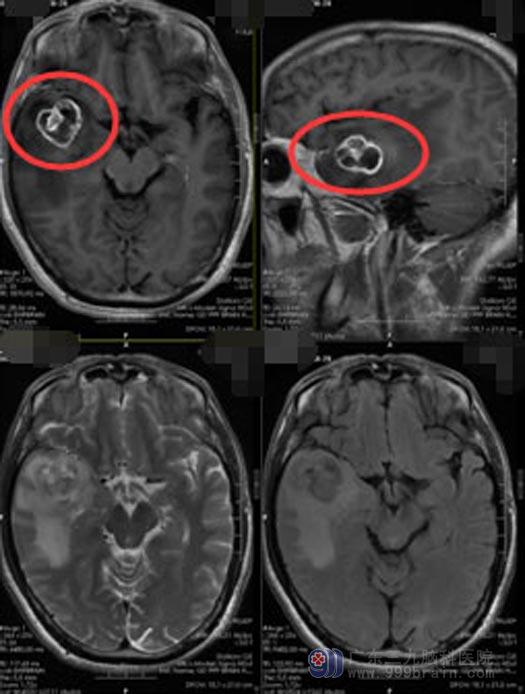

由于当地医院的医疗条件有限,谢先生和家人一起来到了广东三九脑科医院。入住神经外五科后,进一步头颅MR检查提示:右侧颞叶占位性病变,考虑高级别胶质瘤可能性大,完善DWT+ASL+MRS检查后,考虑为右侧颞叶胶质母细胞瘤。

由医院副院长、神经外五科主任鲁明主刀为谢先生实施了“右侧颞叶占位切除术+硬脑膜修补”;术中导航定位,打开皮层可见胶冻状肿瘤,在显微镜下将瘤体分块全切除。经过12个小时的奋战,谢先生安全返回病房。麻醉清醒后,谢先生可以自动睁眼、对答准确、遵嘱活动、四肢肌力肌张力正常,术前担心的并发症均未发生。